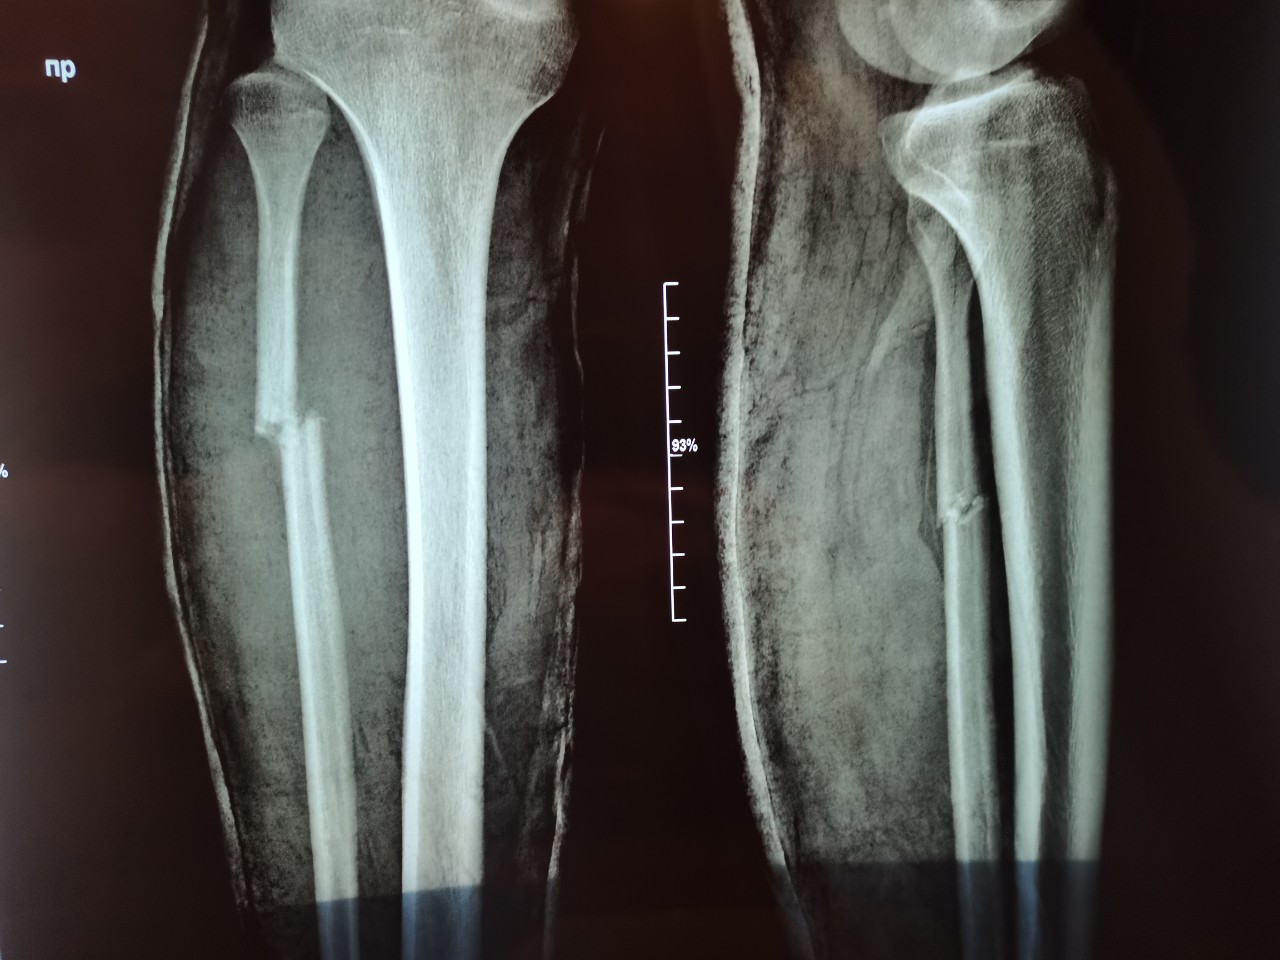

Перелом большой берцовой кости - серьезное повреждение, сопровождающееся болезненными ощущениями и нарушением функции ноги. На этой странице вы найдете много фотографий, позволяющих вам более детально изучить эту травму.

Большеберцовая кость рентген

Здесь представлены медицинские изображения переломов большой берцовой кости, сделанные врачами в процессе диагностики и лечения. Вы сможете увидеть, как выглядит этот тип травмы на рентгеновских снимках и других медицинских изображениях.